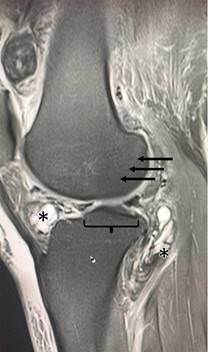

Como parte de la evaluación, se realiza una resonancia magnética nuclear de la rodilla, que revela un edema extenso y difuso en el tejido celular subcutáneo, con afectación de los grupos musculares en la fosa poplítea. Se observan múltiples imágenes quísticas multilobuladas con dimensiones aproximadas de 34 mm, así como nódulos hipointensos en las bursas supra e infrapatelares con dimensiones de 29 mm. Se detecta edema en la porción lateral del cóndilo femoral externo que abarca las regiones anterior y posterior, además de edema en el platillo tibial interno, la región medial de la rótula y signos de lateralización de la rótula, sugestivos de luxación (Figura 1).

Figura 1: Resonancia magnética nuclear de la rodilla afectada. Las llaves muestran la pérdida de la continuidad del borde óseo, así como disminución del espacio articular secundario a la proliferación de tejido sinovial. Las regiones resaltadas con (*) indican proliferación de tejido sinovial con quistes multilobulados en los ligamentos rotulianos. Las flechas indican disminución de la densidad radiográfica asociada a cambios inflamatorios.

La recurrencia de la SVNP se relaciona íntimamente con la persistencia del tejido sinovial afectado en la articulación. Por ende, la identificación de la extensión del daño sinovial es vital para la elección del tratamiento de esta patología.23 La resonancia magnética nuclear es el método imagenológico ideal para el rastreo de las lesiones sinoviales.24 Ya que permite clasificar la SVNP en tres grados distintos: evocativa o inicial, pseudo-coxitis y coxartrosis. Los hallazgos radiográficos típicos incluyen la presencia de lesiones multilobuladas de baja intensidad con incrustaciones de artefactos «en floración», los cuales son secundarios a los depósitos de hemosiderina, así como datos de erosión ósea.25 Estas descripciones coinciden con los elementos distinguidos tanto en el hueco poplíteo como en las regiones perirrotulianas de la paciente de este caso.